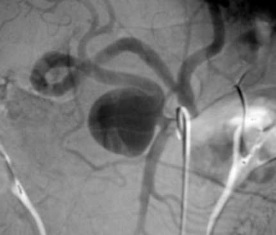

脾动脉瘤栓塞